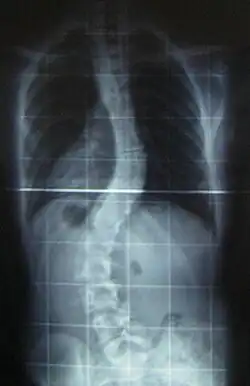

Preoperative (left) and postoperative (right) X-ray of a person with thoracic dextroscoliosis and lumbar levoscoliosis: The X-ray is usually projected anteroposterior, such that the right side of the subject is on the right side of the image; i.e., the subject is viewed from the rear (see left image; the right image is seen from the front). This projection is typically used by spine surgeons, as it is how surgeons see their patients when they are on the operating table (in the prone position). This is the opposite of many Chest radiographs, where the image is posteroanterior, i.e., projected as if looking at the patient from the front. The surgery was a fusion with instrumentation.